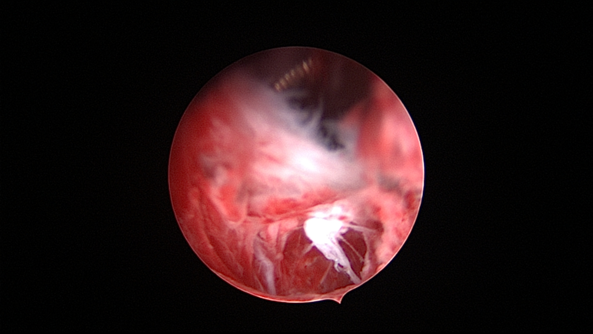

外院取环失败,宫颈暴露困难,缝合牵拉宫颈,尖刀片切开宫颈前唇,扩宫棒顺利扩开宫颈

为了宫腔镜手术平稳顺利进行,宫腔镜术前准备及安全评估非常重要,尤其是充分的安全评估能有效减少并发症的发生。阴道情况:萎缩、纵膈、斜膈等可能导致扩阴器置入困难。肥胖病人、高个子病人阴道很深,宫颈可能难以暴露;宫颈情况:绝经后病人宫颈萎缩、狭窄、坚硬,加之穹隆展平,宫颈难以夹持、难以扩张;宫颈管弯曲、宫颈肌瘤、巨大息肉、粘膜皱襞隐窝、巨大纳囊等,可能阻挡宫腔镜进入宫腔;子宫情况:子宫萎缩,宫腔狭小,子宫极度前屈、后屈、侧屈等极端位置常常导致宫腔镜置入困难;既往盆腔手术史:子宫与盆腔器官粘连可能导致子宫极端位置,或者宫深超出预期。近期手术情况:外院取环失败、人流不全、宫腔探查或试图分粘中途放弃等病人,子宫可能存在假道、穿孔或盆腔积血等损伤。这类病人评估重点:前次手术医院级别、既往分娩情况、安环多少年、月经情况、闭经或绝经时间、手术日期、手术时间长短、是否麻醉、术后有无腹痛、有无阴道出血、B超情况、腹部平片、血糖血压等。宫腔镜术前需再次复查B超,手术医生到B超室了解子宫位置、大小、有无损伤、节育环种类及位置、是否嵌顿、盆腔有无积液等细节。

大多数宫腔镜检查或小手术比较简单,属1~2级手术。直径大于2.5cmⅡ型及以上分型粘膜下肌瘤、胚物残留血供丰富或合并动静脉瘘、胎盘粘连胎盘植入、重度宫腔粘连、绝经时间长生殖器官明显萎缩病人(节育环嵌顿、粘膜下肌瘤、息肉等)、子宫极度前屈后屈侧屈等病例,属3~4级手术,手术可能很困难,手术时间较长,容易出现并发症。宫腔镜手术彻底性跟手术难度及手术效果密切相关,宫腔镜手术不彻底常见,比如节育环残留、胚物残留、纵膈残留、粘连残留等,可能引起感染或医疗纠纷。宫腔镜手术过度少见,纵膈切除过度、分粘过度、内膜切除过度易引起出血及穿孔,熟悉子宫局部解剖、B超或腹腔镜监护可避免或减少手术过度。宫腔镜手术失败罕见(资深医生常能找到解决办法):宫颈无法扩张致手术失败、膨宫不良致手术失败或手术不彻底、术中无法找到节育环放弃手术等偶有发生,需与患者及家属充分沟通,择期再做手术,不要在一条道上走到黑。